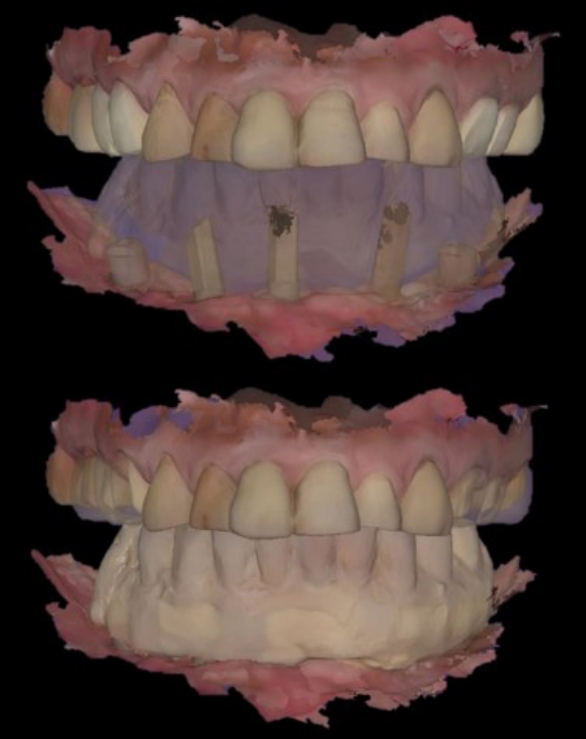

Fig. 13.

The arrangement and design of the all-on-5 prosthesis with a CAD software.